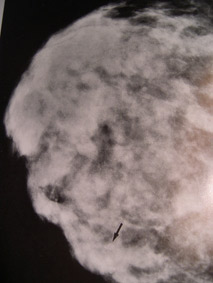

Μαστογραφία σκληρυντικής αδένωσης. Δύσκολο να ξεχωρίσει μια παθολογική σκίαση μέσα σε τόσες άλλες σκιάσεις.

Φυσιολογική  μαστογραφία. Συγκρίνετε με την διπλανή εικόνα και δείτε πόσο πιο εύκολα  θα μπορούσε να φανεί εδώ μια ύποπτη σκίαση καρκίνου αμέσως μόλις θα  αναπτυσσόταν.